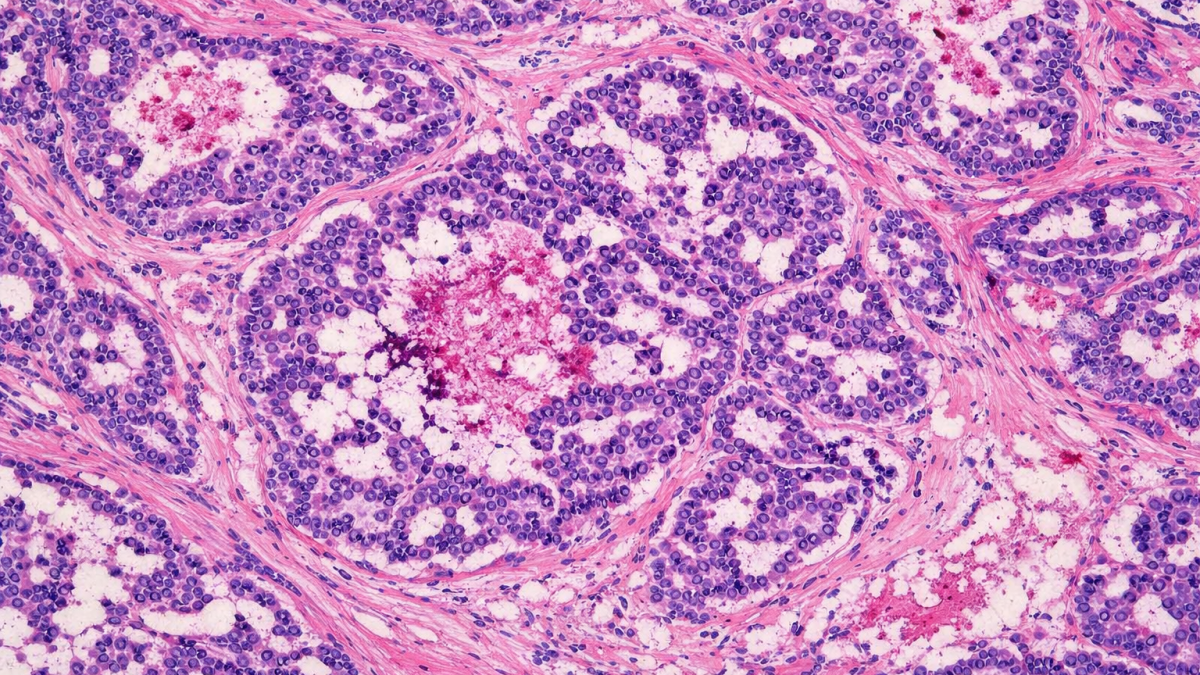

Časopis Journal of Ovarian Research publikoval výsledky výzkumu vědců z Lékařské a Přírodovědecké fakulty MU, CEITEC MU, Masarykova onkologického ústavu a NÚVR věnovaného komplexní genomice high‑grade serózního karcinomu vaječníků.

Autoři provedli komplexní genomické profilování 523 genů asociovaných s nádorovými onemocněními pomocí panelu TruSight Oncology 500 HT v retrospektivní kohortě 42 pacientek s high‑grade serózním karcinomem vaječníků (HGSOC), zahrnující 22 případů senzitivních na deriváty platiny (Pt‑S) a 20 případů primárně rezistentních vůči derivátům platiny (Pt‑R). U čtrnácti pacientek byly analyzovány párové vzorky nádorové tkáně odebrané před zahájením léčby a po neoadjuvantní terapii nebo recidivě onemocnění s cílem posoudit změny ve spektru klinicky relevantních a terapeuticky cílitelných alterací.

Genomické profilování prokázalo výraznou heterogenitu molekulárních nálezů napříč celou kohortou, a to bez ohledu na zařazení do skupin Pt‑S a Pt‑R, přičemž mezi těmito skupinami nebyly zjištěny jednoznačné rozdíly v molekulárním profilu. Pouze amplifikace genu CCNE1 byla častější ve skupině Pt‑R, což odpovídá jeho opakovaně popisované asociací s nepříznivou prognózou. Terapeuticky cílitelné alterace klasifikované podle mezinárodního systému ESCAT (ESMO Scale for Clinical Actionability of molecular Targets) do úrovní I–III byly identifikovány u více než poloviny pacientek v obou skupinách (54,5 % Pt‑S; 55 % Pt‑R). Hypotetické terapeutické cíle odpovídající ESCAT úrovni III byly přítomny přibližně u pětiny analyzovaných případů (18 % Pt‑S; 20 % Pt‑R), což poukazuje na možnosti budoucího rozšíření cílených terapeutických strategií u HGSOC. Více se dočtete zde.